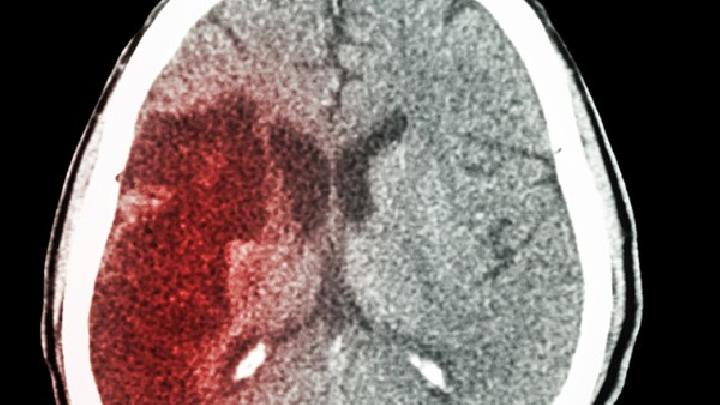

脑栓塞

>